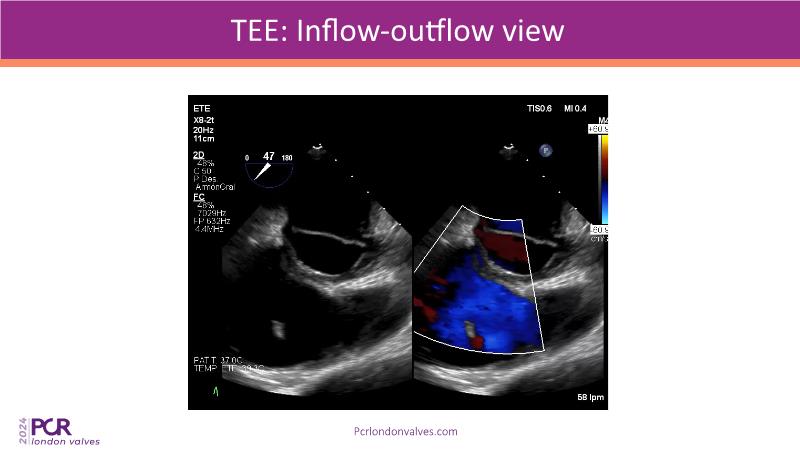

This session examines two compelling cases: a 78-year-old woman with paroxysmal atrial fibrillation, chest trauma, an osteoporotic sternum fracture, and NYHA II exertional dyspnoea, and an 82-year-old man with chronic three-vessel coronary artery disease, bradycardic AF, peripheral arterial disease, spinal stenosis, and chronic kidney disease. Through their study, discover the intricate anatomy of atrioventricular valves, the therapeutic challenges they pose, and the growing significance of transcatheter edge-to-edge repair (TEER) therapies. The discussion also highlights the value of multidisciplinary strategies in managing complex valve diseases effectively.